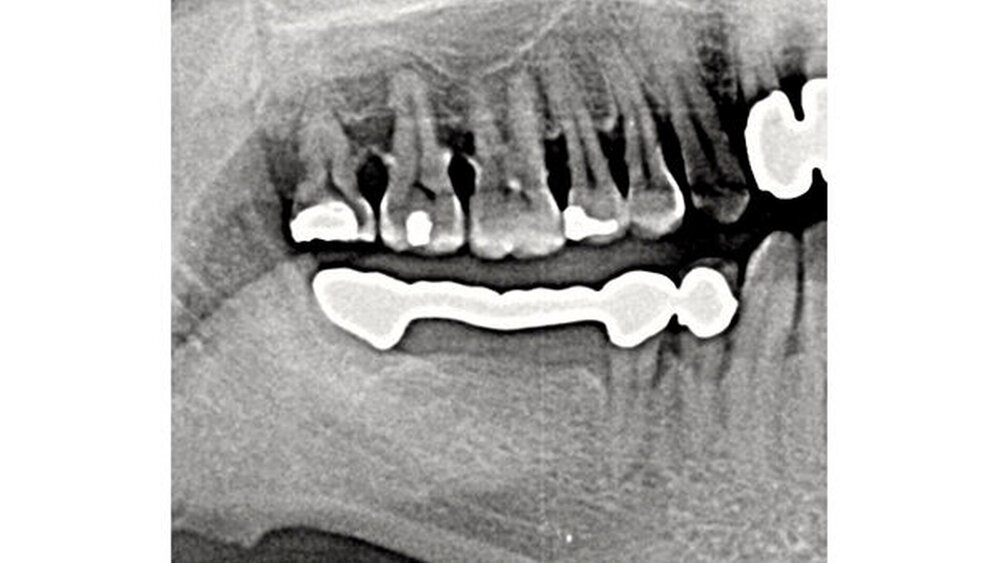

Die Schmerzen betreffen regio 47 bis 48. Ich inspiziere die Region klinisch: Vollguss-Brücke von 44 auf 48, 47 und 46 Zwischenglieder. Der Kronenrand von 48 liegt subgingival, beziehungsweise es fällt auf, dass buccal unterhalb des zu vermutenden Kronenrandes Amalgam angetragen ist.

Meine Verdachtsdiagnose aber bleibt: Kariös zerstörter 48! Zur Unterstützung meines Verdachts mache ich ein OPG. Und dabei erlebe ich die Überraschung: Und glauben Sie mir, ich schaute dreimal hin: Röntgenartefakt? Projektionsfehler? Ich überlegte wirklich kurz, mit welcher anderen Projektion ich diese Wurzel denn darstellen könnte. Die Brücke war sehr alt und musste sowieso runter. Ich handelte. Und war erneut sehr überrascht.

Und der Patient konnte sich dann nach bohrendem Nachfragen auch wieder erinnern: „Ja, ja, da hatte ich schon einmal Beschwerden. Da hat mein Zahnarzt die Brücke heruntergenommen, irgendetwas gemacht und die Brücke wieder eingesetzt. Die Beschwerden gingen weg."